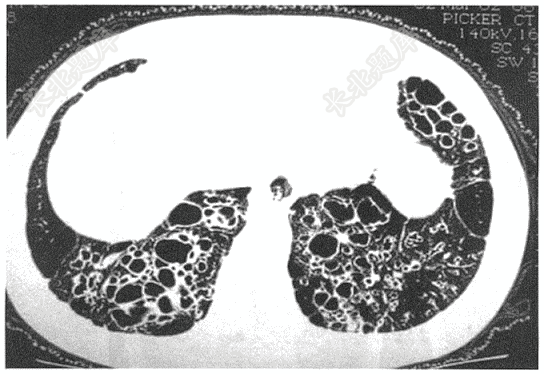

- 单项选择题患者男,70岁,因反复咳嗽、咳脓痰20余年,活动后气促3年,加重3天入院。入院体查:双下肺可闻及散在湿性啰音,有杵状指。肺部HRCT如下图,考虑诊断为( )

A、肺大疱并感染

B、支气管扩张并感染

C、特发性肺间质纤维化

D、气胸

E、肺淋巴管肌瘤病